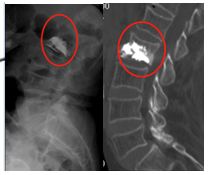

谭奶奶术后复查腰椎X线及CT

新型支架成形技术能很好的复位骨折椎体及维持复位后椎体高度。术中能预制空腔,有效减少术中骨水泥渗漏。另外金属支架与骨水泥很好的吻合,可能增加术后早期强化椎体的稳定性。